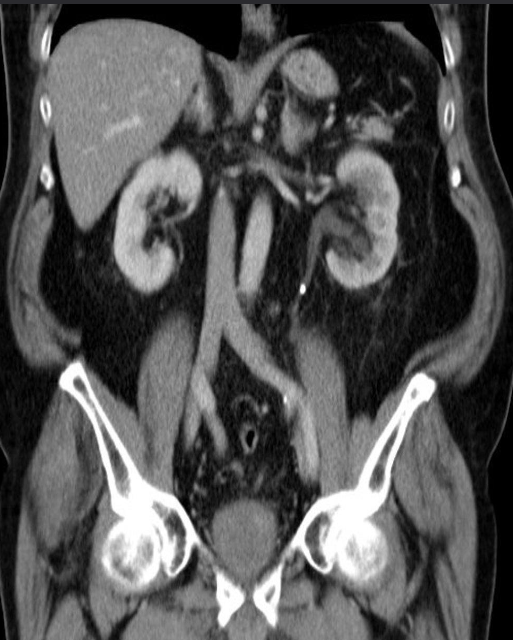

Polycystic kidneys disease

CT abdomen (with contrast; coronal plane) Both kidneys are markedly enlarged and feature multiple round-to-ovoid, hypodense lesions of various sizes compatible with cysts. Some smaller cysts are present in the liver.

The CT features are consistent with autosomal dominant polycystic kidney disease (ADPKD).

2nd img Polycystic kidneys disease CT scan, taken after intravenous contrast enhancement, showing that both kidneys are greatly enlarged and almost entirely replaced by cysts of variable size.